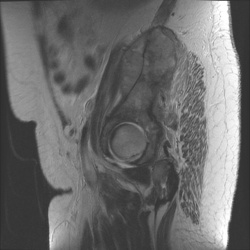

25.08.2011 - 12:21

Пациентка поступила в клинику с жалобами на подъём температуры, боли в левой подвздошной области. . Менопауза 6 лет. Варианты? (Ответ знаю). :-)